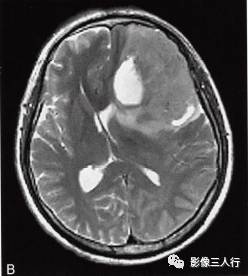

左侧额颞叶多形性胶质母细胞瘤

A.T1WI横断面;B.T2WI横断面;CFLAIR横断面;D.T1WI增强;E.T1WI增强冠状面;F.T1WI增强矢状面;G.HE×40;H.GFAR( )×40

影像学表现:

左侧额颞叶见较大不规则囊实性肿块,大小约5.4cm×8.3cm,平扫T1WI呈低信号、T2WI呈高信号(图A、B),肿块内有斑片状囊变区;增强扫描肿块实性部分呈不均匀明显强化,囊性部分呈环形强化(图D~F)。肿块占位效应明显,周围见环形水肿(图C)。